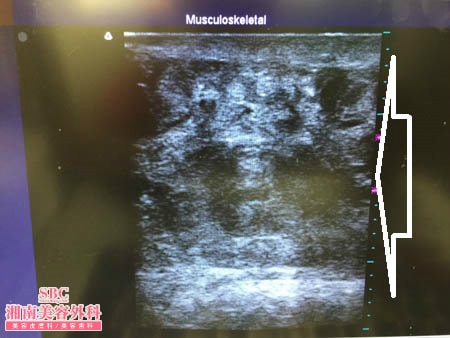

No.174554【脂肪吸引】【動画あり!】湘南美容外科・全ドクターの脂肪吸引総括指導医であるあの有名な根こそぎ竹田先生の劇的ビフォーアフター!香港在住の中国人の患者様の太ももを細くする!術中3Dタッチビュー・左太もも後面